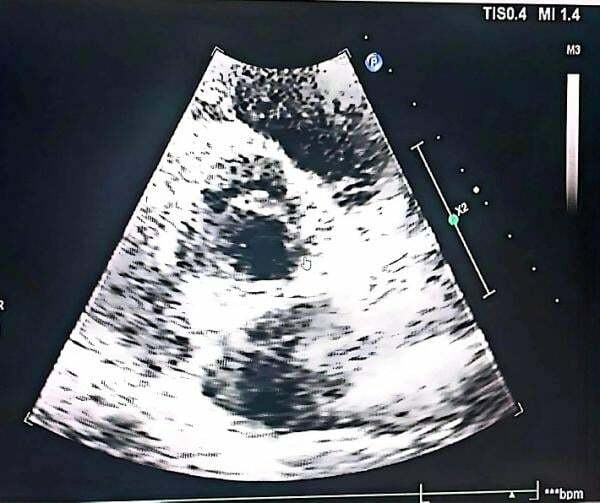

該院心血管內科主治醫師李磊詳細檢查發現,雖然患者描述的症狀類似心絞痛,但其本人並沒有「三高」和菸酒等冠心病高危因素,心電圖也沒有發現明顯的心肌缺血徵兆。不過,李磊在聽診中發現患者主動脈瓣聽診區有明顯的心臟舒張期瓣膜雜音,接下來的心臟超聲檢查證實患者出現主動脈瓣二瓣化、主動脈瓣重度關閉不全,最終導致其反覆胸悶。

該院心血管內科主任胡立群解釋,人類的心臟內共有四組瓣膜,即主動脈瓣、肺動脈瓣、二尖瓣、三尖瓣,它們相當於心臟中的「單向閥」,通過周期性開閉確保血流的方向正常。如果主動脈瓣發生關閉不全,就會造成血液回流,加重心臟負荷,導致左心室擴張,引發一系列心血管疾病。除了反覆胸悶,隨著病情發展還會出現心悸、呼吸困難、心絞痛等。